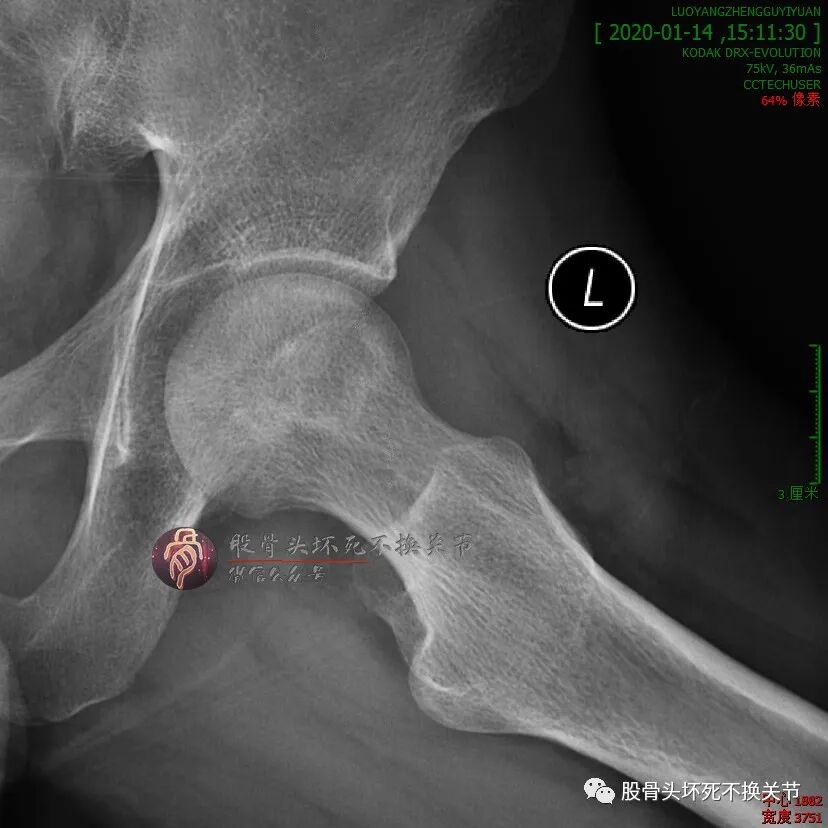

来,试试看。第一回合,住院治疗一个疗程,先缓解疼痛。4个月后复查:

尽管解决了疼痛问题,但复查时显示骨密度并没有太大的改变。